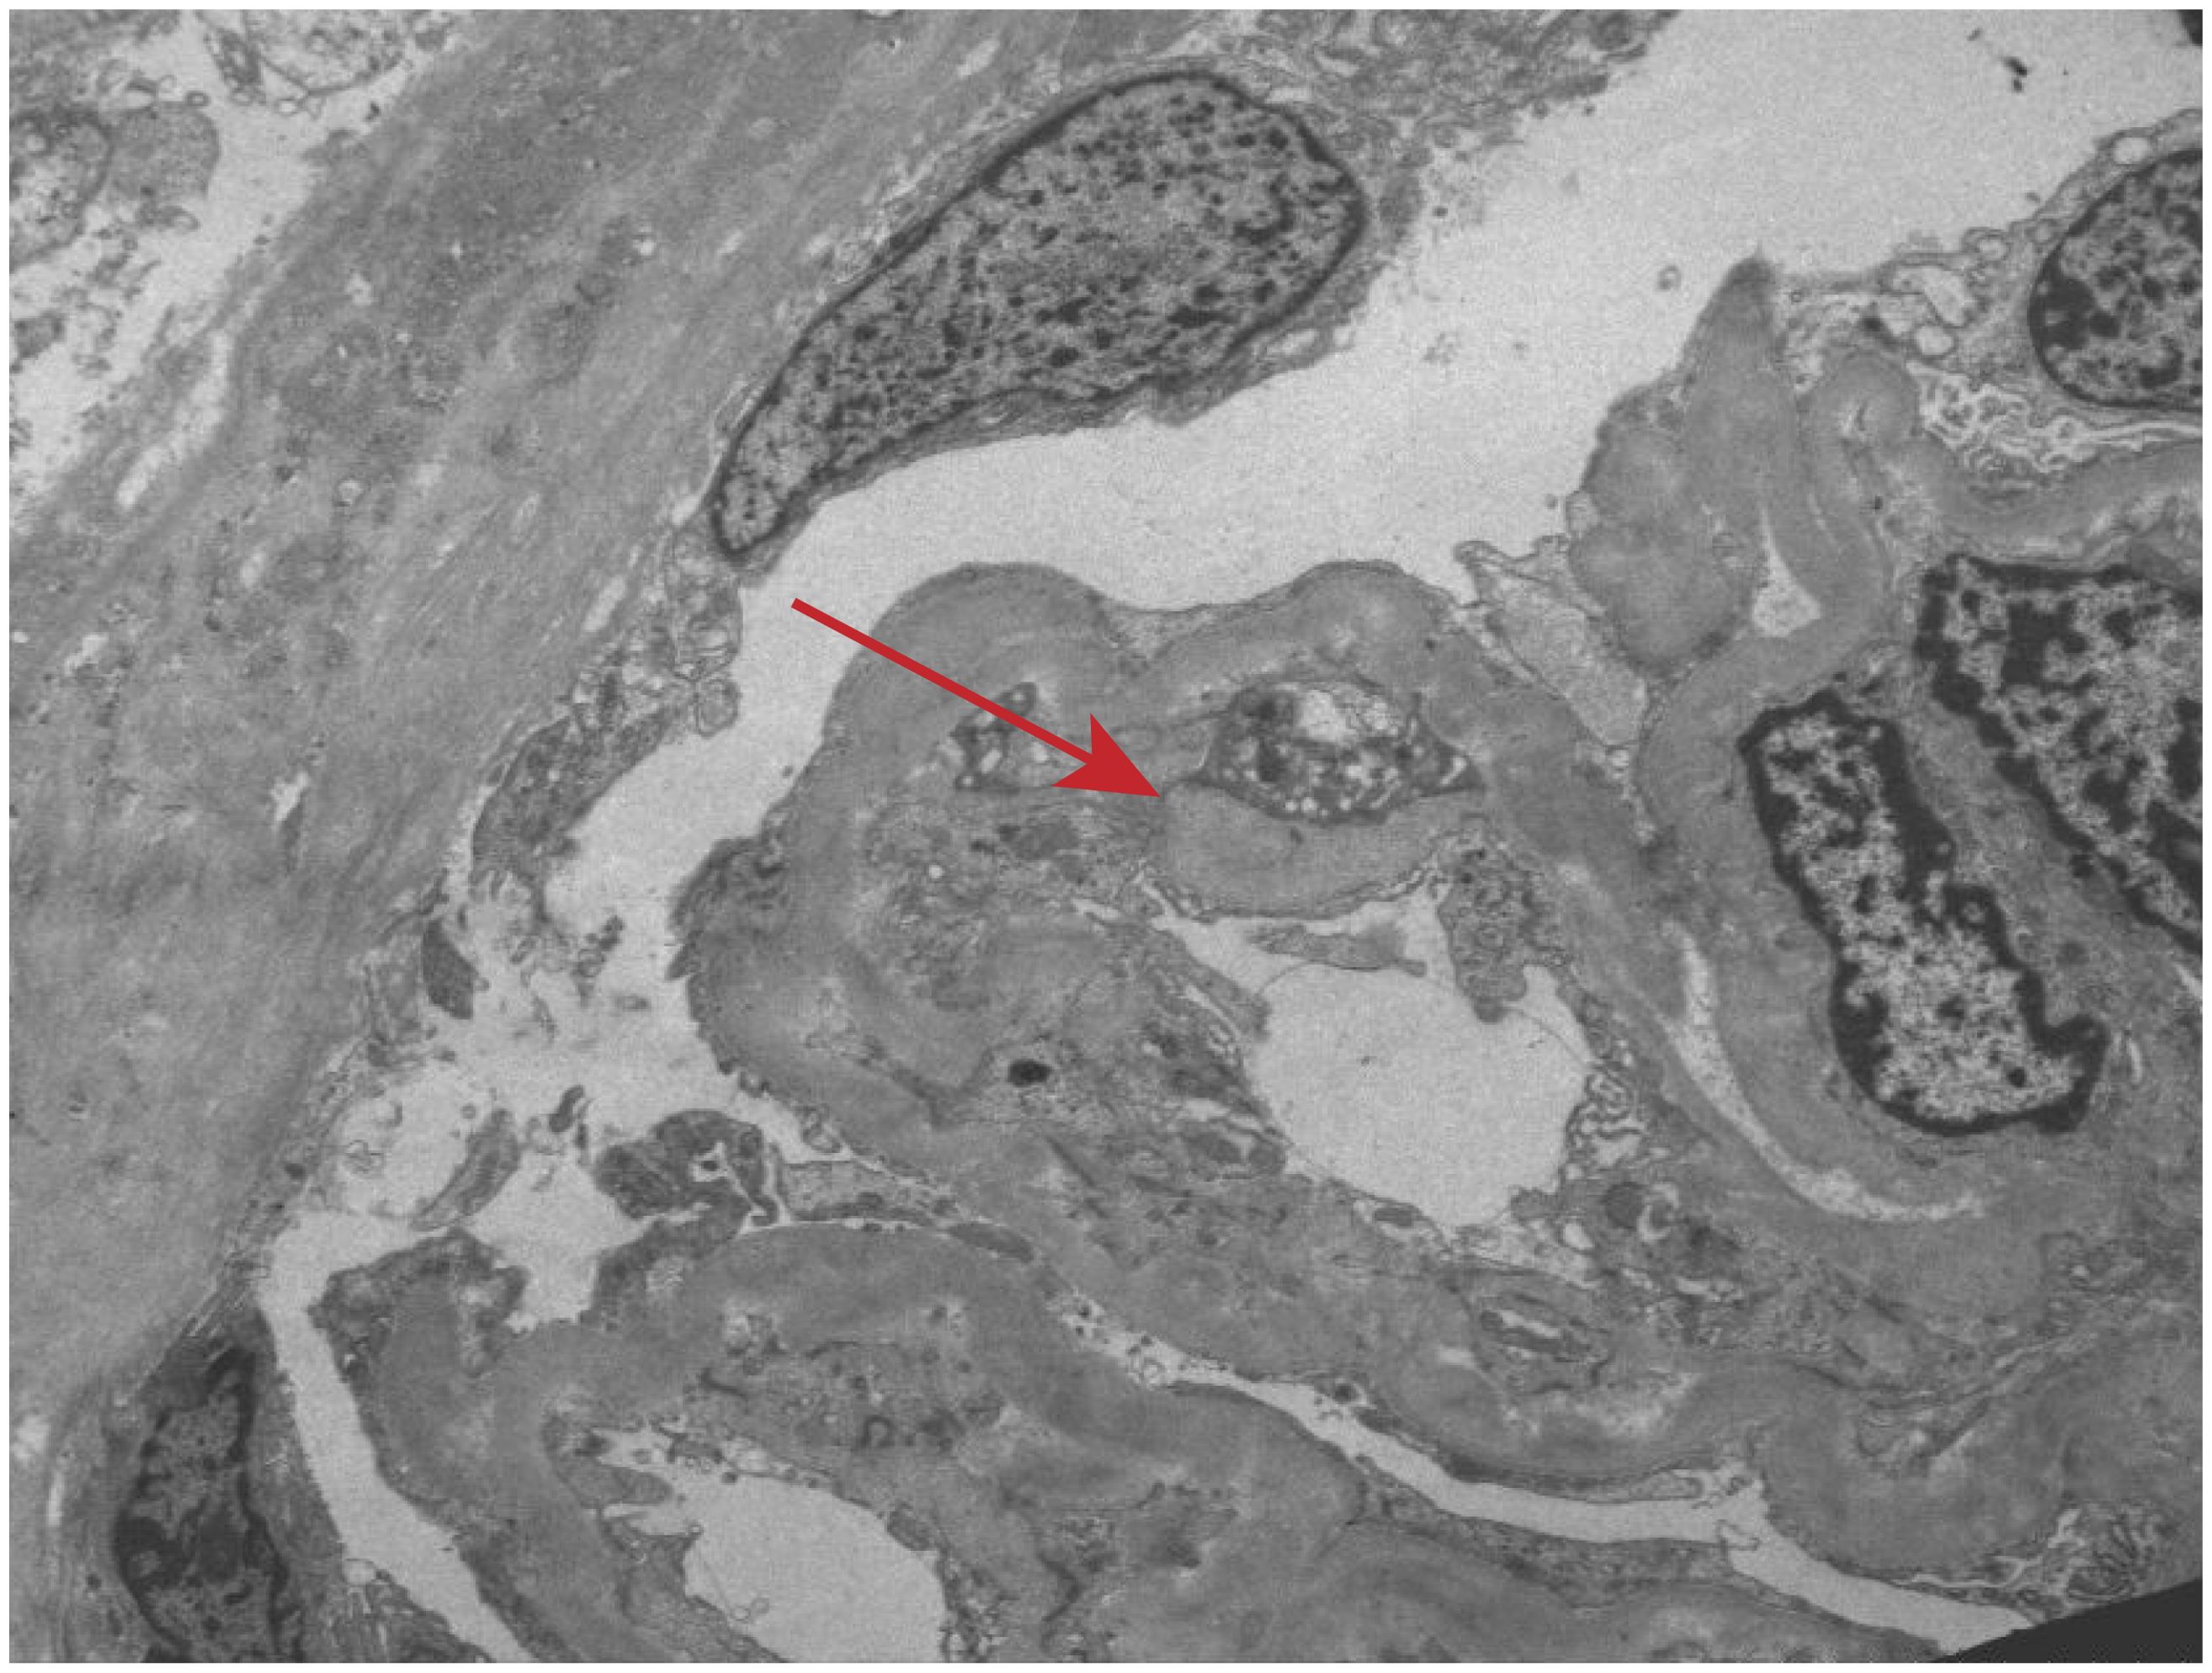

Renal biopsy was performed two days after admission, revealing significant pathological changes across all microscopic modalities. Light microscopy demonstrated advanced glomerular damage with 10 out of 12 glomeruli showing global sclerosis, while the remaining two exhibited segmental sclerosis and adhesion of Bowman’s capsule. The GBM displayed spherical vacuolar degeneration with shrinkage, accompanied by partial capillary lumen occlusion. Tubulointerstitial involvement was prominent, featuring approximately 60% tubular atrophy with moderate to severe epithelial cell degeneration, focal tubular dilatation, and epithelial cell shedding. The interstitium showed matching 60% fibrosis with lymphocytic, monocytic, and neutrophilic infiltration (Figure 1). Immunofluorescence studies of paraffin-embedded tissue revealed dual deposition patterns: mesangial IgA (++) and complement C3 (++), consistent with HSPN, along with linear IgG (+++) deposition along glomerular capillary walls, suggestive of anti-GBM nephritis (Figure 2). Electron microscopy further confirmed irregular thickening and rupture of GBM, ischemic glomerular changes accompanied by mesangial proliferation and extensive foot process fusion (Figure 3). The comprehensive histopathological evaluation supported a final diagnosis of sclerosing glomerulonephritis, with the collective findings most compatible with HSPN and concurrent anti-GBM antibody-mediated renal damage, particularly given the characteristic linear IgG deposition pattern.

Figure 3. Electron microscopic observation. Irregular thickening and rupture of GBM, ischemic glomerular changes accompanied by mesangial proliferation and extensive foot process fusion (red arrow).